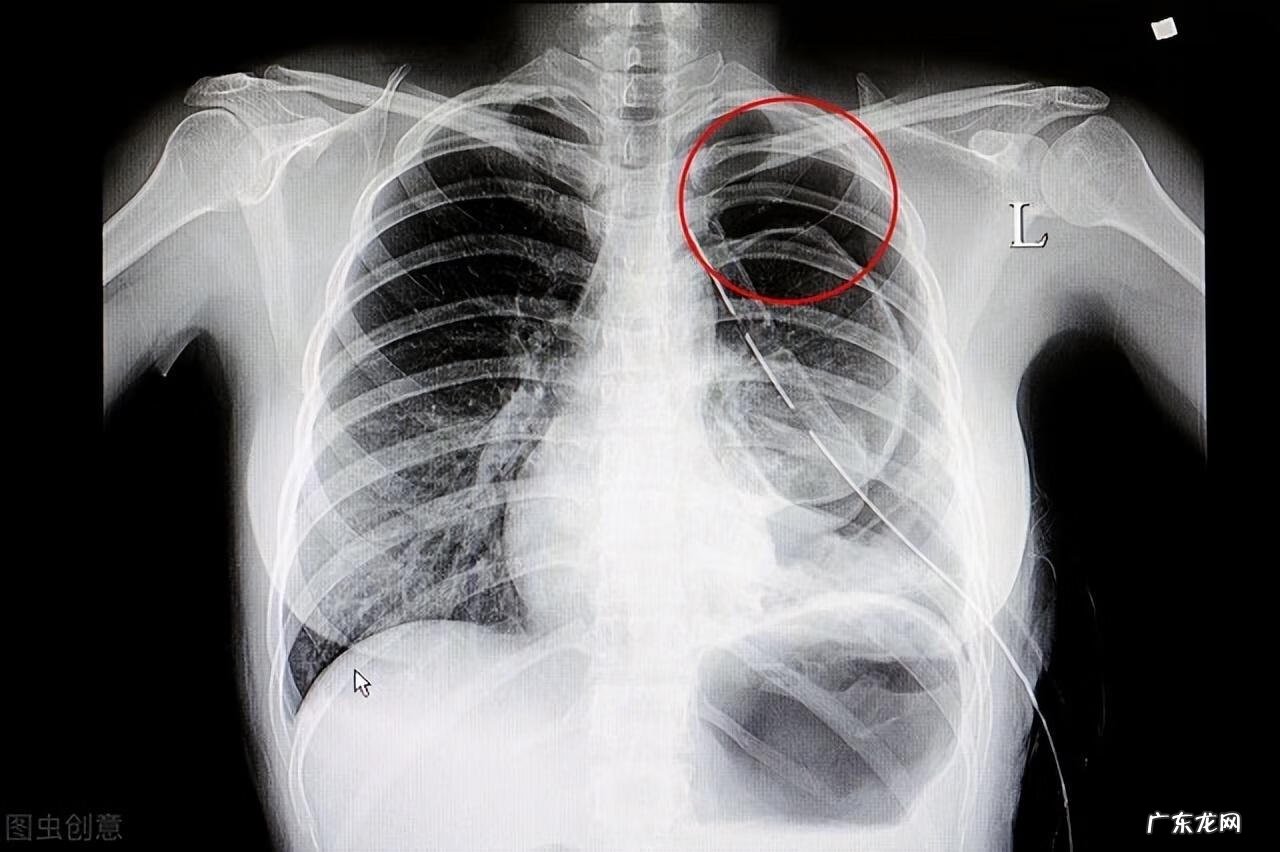

气胸有症状吗?有 , 主要有三个症状:1.呼吸困难;2.胸痛;3.刺激性干咳

气胸根据胸腔内压力及病理生理改变 , 可分为:闭合性气胸、交通性气胸、张力性气胸 。

闭合性气胸 , 可以直接理解为胸膜裂口处被渗出物封闭 , 导致空气不再进入胸腔 , 形成局部的固定量空气在胸膜腔 , 导致胸膜腔压力高于大气压 。

交通性气胸 , 可以直接理解为胸膜裂口处因粘连或者周围纤维固定成一扇双向门 , 气体可以经过这扇门自由进出胸腔 , 导致胸膜腔压力在大气压上下波动 。

张力性气胸(最危险的) , 可以直接理解为胸膜裂口因粘连或者周围纤维固定成一扇单向门 , 气体只进不出 , 导致胸膜腔压力持续升高 , 最终可能导致纵隔偏摆 , 心脏骤停 。